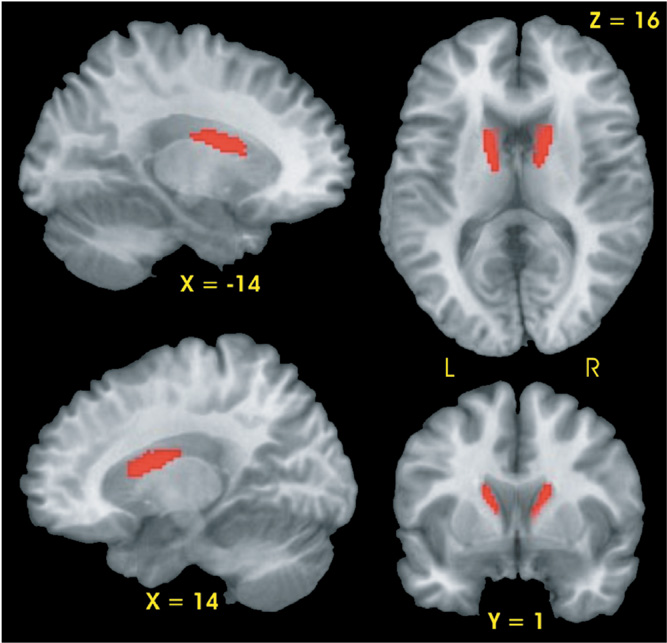

Voxel-Based Morphometry

Planned contrasts demonstrated that the CLOSE group had two regions, the right and left head and body of the caudate, with smaller gray matter volumes relative to the CONT group (see Fig. 1). No differences in gray matter volume were observed between the FAR and CONT groups nor between the FAR and CLOSE groups.

Results of voxel-based morphometric analysis. Significantly smaller gray matter volume (red region) was observed in the bilateral caudate of the CLOSE group relative to the Control group.

We used two methods for examining structural anatomic differences across participant groups. The first method involved tracing the volume of the caudate and putamen. The second method, VBM, was used primarily to examine regional group differences in cortical gray matter volume. In addition, the VBM method enabled a comparison with the tracing method for identifying volumetric differences in the caudate and putamen across groups. Both methods identified atrophy of the caudate in the CLOSE group, but VBM did not find atrophy of the putamen. In addition, the tracing method was able to identify a small, but significant reduction in the % caudate ratio for the FAR group (Table 2); the VBM method did not find any differences between the FAR and CONT groups. These results would suggest that despite the ease of implementing VBM on a whole brain basis, this method may not be as sensitive to identifying regional changes in gray matter volume compared to more traditional methods of tracing predefined ROIs (Davatzikos, 2004).